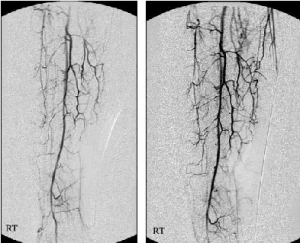

삼성서울병원 김동익 교수팀(혈관외과)는 지난 2003년 3월부터 2004년 12월까지 버거씨병 환자 27명의 하지에 자가골수줄기세포를 근육에 이식하는 치료를 시행한 결과 73%(22명)에서 새로운 측부혈관이 생성되는 효과를 입증했다고 18일 밝혔다.

김동익 교수는 “기존 골수이식세포 이식방법을 개선한 결과 치료방식이 더 간편해지고 치료기간이 단축됐을 뿐 아니라 치료 효과도 우수한 것으로 나타났다”며 “앞으로 더 많은 연구가 진행된다면 심근경색, 말초동맥 폐색, 뇌경색에 이르기까지 광범위한 질환 치료에 적용할 수 있을 것”이라고 말했다.